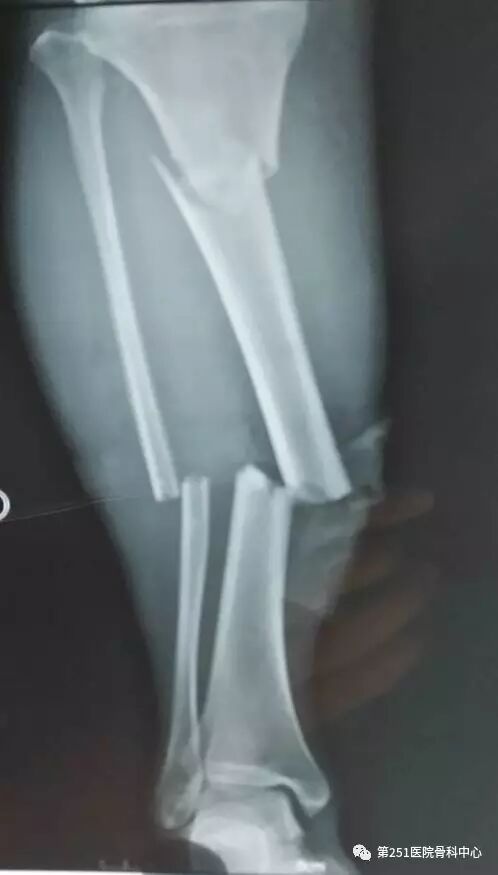

病例1:男性,40岁,车祸伤,胫腓骨多段骨折。

![]()